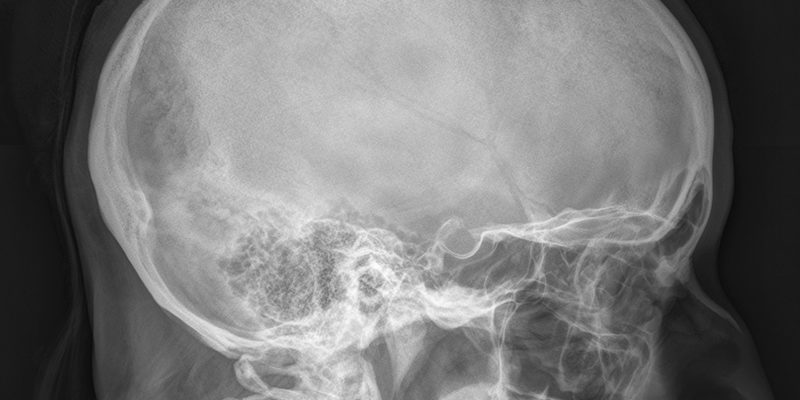

Рентгеновские снимки делаются в следующих проекциях:

- прямой лобовой;

- правая и левая сторона;

- правая и левая сторона; и правая и правая задняя.

Часто выполняется дополнительная обзорная рентгенография черепа. Это измерение позволяет определить размер и форму турецкого седла по сравнению с аналогичными характеристиками черепа.

Рентгенологическую карту составляет рентгенолог. Специалист оценивает размерные параметры, форму, контур и состояние костей.

Многие из следующих параметров имеют диагностическое значение:

- Сагиттальный размер: правильное значение 9-15 мм.

- Вертикальный размер: нормальное значение 7-12 мм;

- Индекс седла: сравнительный индекс высоты и длины седла. У здоровых детей это количество больше единицы, у взрослых чуть меньше.